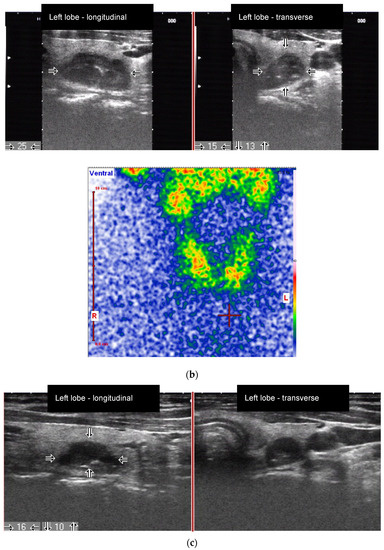

Figure 3.

Male patient with an autonomously functioning thyroid nodule (AFTN) (scintigraphy with 99mTc-pertechnetate) in the left thyroid lobe (25 × 27 × 36 mm; nodule volume 12.2 mL, arrows). (a) Before radioiodine therapy (RIT) (2016, TSH value 0.06 mU/L, no thyroid medications) with 1033 MBq (206 Gy due to reduced half-time at therapy). TIRADS classification: Kwak-TIRADS 4A (taller-than-wide shape); EU-TIRADS 5 (taller-than-wide shape); (b) The same patient 6 months after RIT (follow-up 1, FU1). The thyroid nodule size decreased to 15 × 13 × 25 mm (volume: 2.4 mL, arrows). Scintigraphy with 99mTc-pertechnetate shows a non-hyperfunctioning area in the left lobe. TIRADS classification: Kwak-TIRADS 4C (predominantly solid composition, hypoechoic, microcalcifications); EU-TIRADS 5 (microcalcifications); (c) The same patient 12 months after RIT (TSH value 1.4 mU/L, Levothyroxine 50 micrograms/day). The thyroid nodule size at FU2 was 10 × 16 mm (arrows). TIRADS classification: Kwak-TIRADS 4C (solid composition, markedly hypoechoic, microcalcifications and macrocalcification); EU-TIRADS 5 (marked hypoechogenicity, microcalcifications).